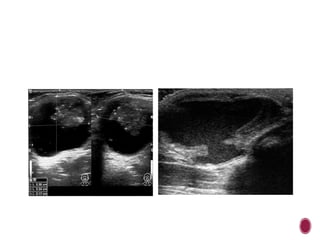

 Transverse US image of

follicular adenoma in a

34-year-old woman

shows a welldefined

smooth, ovoid-shaped,

and hypoechoic nodule.

There are no micro-or

macrocalcifications